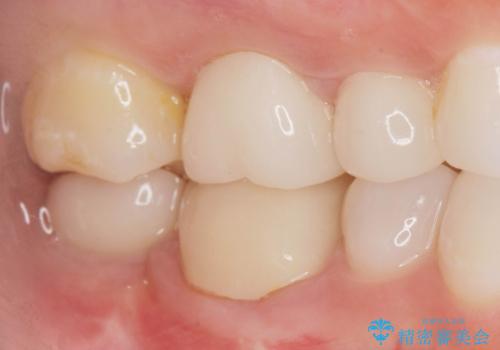

伸びてしまった奥歯、咬合平面を揃えたインプラント治療

- 右下の歯を虫歯で抜去し、インプラント治療を希望され来院されました。

インプラントを埋入するのに十分な骨は存在しますが、放置した間に上の歯が伸びてきてしまいクラウンのスペース不足な状態です。

通常このような場合、神経を除去し歯を短くしたのちインプラント治療を行いますが、今回はマイクロインプラントを用いて歯を歯ぐきの方向へ沈めたのち神経を温存する形でインプラント補綴を行いました。

伸びてしまった上の奥歯を、神経もとらず、クラウンにもせず治療することができ、喜んでいただくことができました。